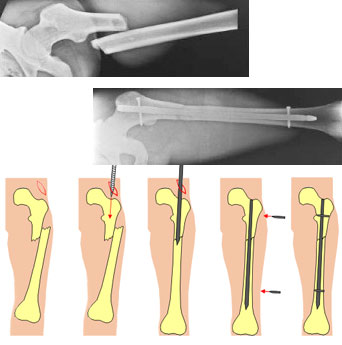

Pose Estimation of Cylindrical Objects for a Semi-Automated Fracture Reduction - Summary

Below we present the results of our method for computing the relative target transformations between broken cylindrical objects in 3d space.

我们首先计算的位置和方向the axes of every cylindrical object. This is achieved by a specially adapted Hough transform. These axes are the most important attributes for the segmentation of fractured bones and can also be used as an initial pose estimation (constraining 4 of the overall 6 degrees of freedom of the reduction problem).

After these preprocessing steps, the relative transformation between corresponding fracture segments can be computed using well-known surface registration algorithms. Here we are using a special 2D depth image correlation and a variant of the ICP (Iterative Closest Point) algorithm. A project goal is using these methods for computing the target poses of bone fragments in order to allow for a computer assisted semi-automated fracture reduction by means of a robot.

Fracture Reduction using a Telemanipulator with Haptical Feedback - Summary

我们开发了一个复杂的系统,which allowed to use a robot as telemanipulator for supporting the fracture reduction process. Our robot is a standard industrial Säubli RX 90 robot. The robot is controlled by the surgeon by means of a Joystick with haptical feedback. Intraoperative 3D imaging of the fracture is the base information for the surgeon during reduction. These 3D volume images are automatically segmented by the PC resulting in highly detailed surface models of the fracture segments (cp. the figure below), which can be used by the surgeon to precisely move the fragments to the desired target poses. An optical navigation system ensures that the 3D scene presented on the PC display is always in accordance with the real surgical situation; the virtual 3D models always move in the same way as the real bone fragments, which are moved by the robot.

All forces and torques acting in the operation site can be measured by means of a force/torque sensor mounted at to robots hand. These forces are fed back to the joystick. This way, the surgeon is able to feel the forces acting on the patient because of distracted muscles or contacts between the fracture segments.

Results

In a first test series, the telemanipulator system was evaluated in our anatomy lab using broken human bones (without surrounding soft tissue). It could be shown that reduction accuracies with mean values of about 2° and 2mm can be achieved for simple fractures. Even for complex fractures the achievable accuracy stays below 4°. From a clinical point of view, these values are more than acceptable.

Furthermore, the telemanipulator system was also tested on human cadavers; complete specimens with intact soft tissues around the broken bone. The results have been similar to those outlined above. In addition we could show that to telemanipulated reductions achieve significantly higher reduction accuracies than manual reductions, which have been performed by an experienced surgeon on the same fractures.

Conclusion

The presented form of visualization and interaction with a telemanipulator system for fracture reduction in the femur turned out to be efficient and intuitive. All test persons have been able to perform reliable reductions with high reduction accuracies after only a short time of learning. These results clearly show the potential of robotized fracture reduction, which will ensure high quality outcomes of such operations in the future.